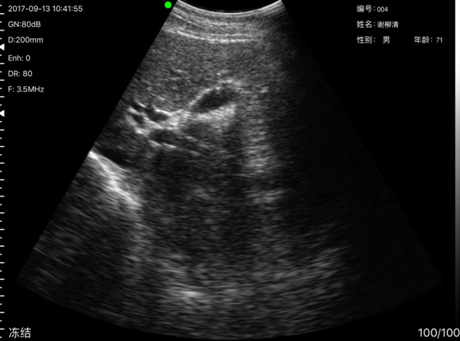

病例5,姓名:谢x清,性别:男,年龄:71岁,本次发现其胆囊周边有异物,经到上级医院复查为胆囊息肉。